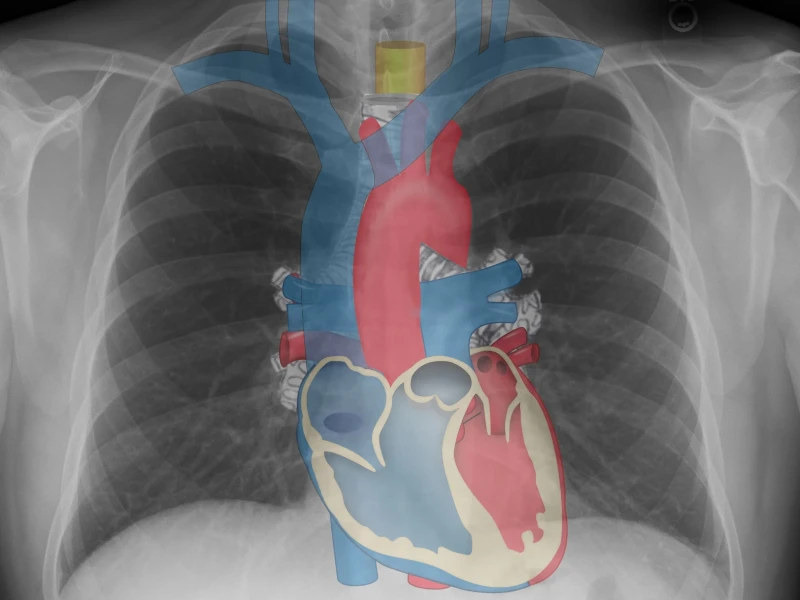

Radiografía de tórax

- ABCDEF — Post de mnemotecnia (publicado): “Informe de la radiografía de tórax: Mnemotecnia ABCDEF”.

- Guía aplicada (publicada): “Cómo interpretar una radiografía de tórax”.